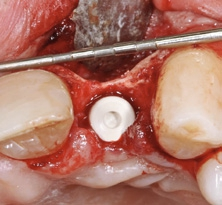

Mit der PEEK-Abdeckkappe, die über einen Klickmechanismus in die Innenkonfiguration des Implantats gesteckt wird, wurde das Implantat verschlossen. Die Abbildung 10 zeigt die optimale prothetisch orientierte Platzierung des Implantats für die Rekonstruktion mit einer direkt verschraubten Hybridabutmentkrone. Von okklusal ist das ausgeprägte bukkale Knochendefizit deutlich zu sehen. Mit einem Gemisch aus autologen Knochenspänen, die während des Bohrvorgangs implantatnah gewonnen worden waren, und Bio-Oss Collagen (Geistlich) wurde der Defekt aufgebaut. Aufgrund ihrer osteogenetischen, -induktiven und -konduktiven Eigenschaften ist der Einsatz von autologen Knochenspänen in der GBR in unserer Praxis Standard. Eine resorbierbare Membran mit verlängerter Barrierefunktion (Memlok BioHorizons) wurde nach Ablösung des Periosts, dem biologischen Konzept folgend, zur Abdeckung des volumengebenden Augmentats in direktem Kontakt zur angrenzenden Knochenoberfläche eingebracht (Abb. 11) [17, 18]. Resorbierbare Kollagenmembranen zeichnen sich dadurch aus, dass der Heilungsprozess der Weichgewebe auch bei Exposition der Membran weiter voranschreitet. Ein Kollagenkegel (Parasorb, Resorba) wurde zum Verschluss des gingivalen Defektbereichs eingesetzt, bevor das Weichgewebe spannungsfrei vernäht (Prolene 5-0, Ethicon) und ein postoperatives Röntgenkontrollbild gemacht wurde (Abb. 12–14). Die temporäre Versorgung erfolgte durch eine Kunststoff-Klebebrücke.